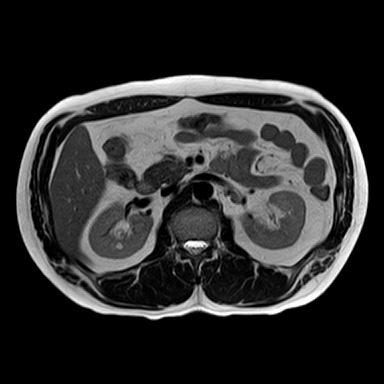

신장 양쪽에 혹이 있다고 하는데 (좌신, 등)

• 1번 째 사진

• 비뇨기과를 가시는 것이 맞고, 제공해주신 MRI와 초음파 소견을 종합하면, 양측 신장에 병변이 보이기는 하나 형태가 서로 다릅니다. 한쪽은 비교적 경계가 명확하고 밝게 보이는 병변으로 낭종 가능성이 우선 고려되고, 반대쪽은 내부 신호가 혼재된 형태로 단순 낭종 외의 병변 가능성도 완전히 배제하기는 어렵습니다. 다만 단일 컷 이미지로는 조영 증강 여부, 내부 구조, 혈류 평가가 제한되어 확정 판단은 불가능합니다.

임상적으로 중요한 기준은 단순 낭종인지, 복합 낭종인지, 혹은 고형 종양인지 구분하는 것입니다. 단순 낭종이면 추가 치료 없이 경과관찰이 원칙이고, 복합 낭종이나 고형 병변이면 추가 평가가 필요합니다. 이 구분은 조영증강 CT 또는 조영 MRI에서 보스니악 분류 기준으로 판단합니다.

진료과 선택은 비뇨기과가 우선입니다. 신장 종양 및 낭종의 1차 평가와 추적, 필요 시 수술까지 담당하는 과입니다. 영상의학과는 판독을 담당하는 과로 직접 진료는 하지 않으며, 신장내과는 기능 이상이나 만성신질환이 있을 때 적합합니다.

권장 흐름은 다음과 같습니다. 현재 MRI 원본과 판독지 확보 → 비뇨기과 방문 → 필요 시 조영 CT 또는 조영 MRI 추가 (만약 수술적 치료를 계획한다면 신혈관 파악이 용이한 3D renal angio CT 등 추가 촬영할 수도 있습니다.)→ 보스니악 분류에 따른 추적 또는 치료 결정입니다.

현 시점에서 급하게 의심할 소견으로 단정하기는 어렵지만, 양측성 병변이므로 단순 낭종인지 확인은 반드시 필요합니다. 특히 40대에서는 우연히 발견되는 낭종이 흔하지만, 복합 낭종은 일부에서 종양과 연관될 수 있어 정밀평가가 필요합니다.